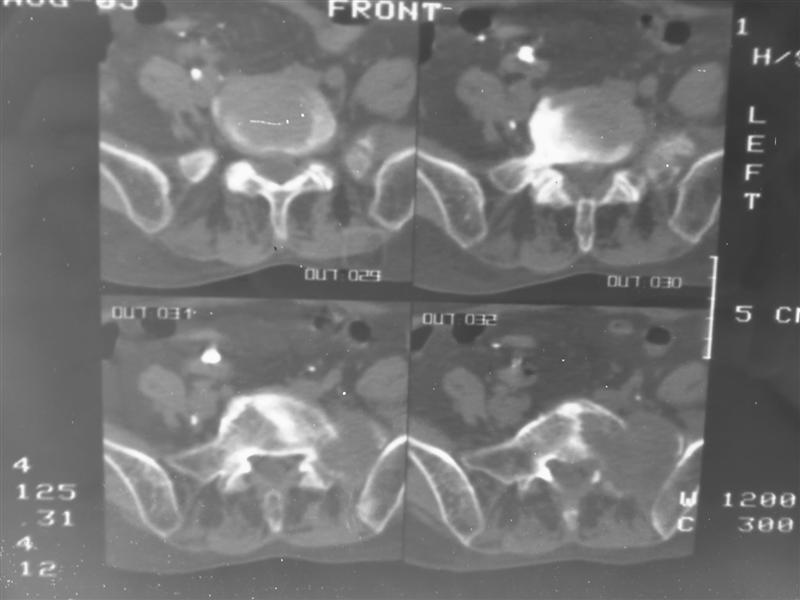

以下是引用老爱克斯新网客在2007-9-27 17:59:00的发言:[br]多个椎体及椎弓跟骨质破坏,并见软组织肿块,符合转移瘤改变,

以下是引用wqs571018在2007-9-27 16:48:00的发言:[br]支持:多发病变,骨质破坏伴软组织块影,符合转移.